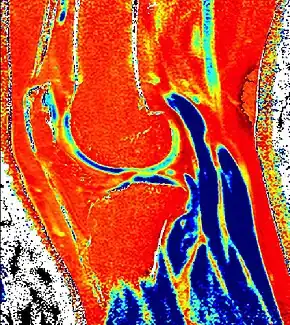

dGEMRIC T1 Map of knee cartilage

Purposemeasures relative proteoglycan content of articular cartilage

Delayed gadolinium-enhanced magnetic resonance imaging of cartilage or dGEMRIC measures the fixed-charge density and relative proteoglycan content of articular cartilage using the spin-lattice relaxation time or T1 relaxation time.[1] Current research is investigating the clinical application of dGEMRIC as a quantitative tool for monitoring cartilage function in diseased or repair cartilage.[2]